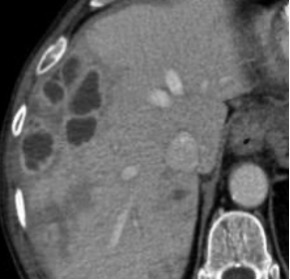

Aspetto TC

- Formazione ben definita, a margini netti, ipodensa (< 20 HU), dotata di enhancement globulare e periferico con riempimento centripeto e iperdensità tardiva.